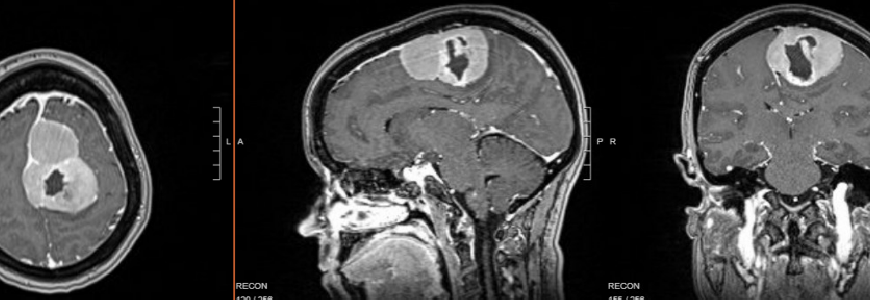

MRI of meningioma preop

An MRI completed in the ER revealed a 6.9 cm by 5.0 cm by 4.4 cm meningioma in the anterior-posterior direction. She had experienced decreased motor function on her right side, a persistent headache, and a tonic contraction of the foot and leg tightening for several weeks leading up to the seizure.

The patient was then transferred to Duke for further evaluation. “The mass was in the parasagittal region of the brain, and it was directly compressing on the part of the brain controlling right leg movement,” says Patel.

Patel continues, “Resecting tumors in this location is challenging because they can contact the motor cortex. We also had to consider maintaining the integrity of the sagittal sinus and the collateral cortical veins. Interrupting the venous flow can cause severe swelling in the brain and is potentially life-threatening.”